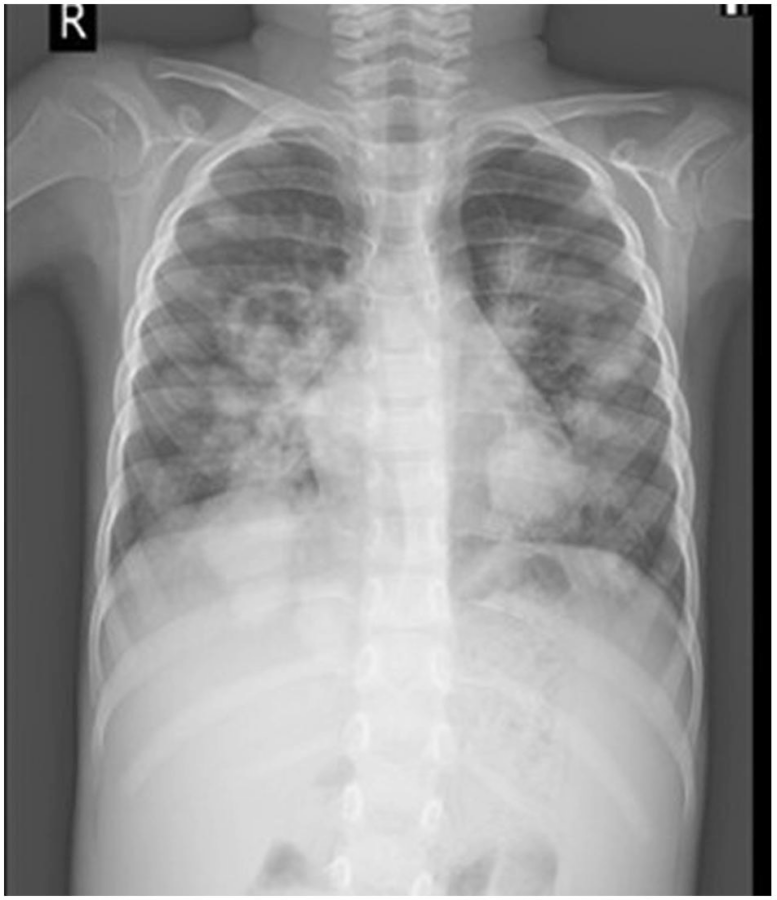

34-year-old man found down after two-week illness

A 34-year-old man with no significant medical history presented to the emergency department after being found on the floor in his room after returning from Southeast Asia two months prior.